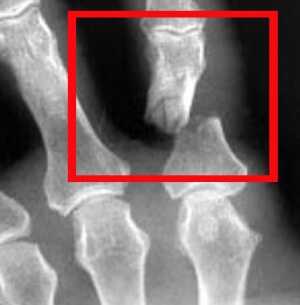

ΠΠ»Ρ Π²ΡΡΠ²Π»Π΅Π½ΠΈΡ ΠΏΠ΅ΡΠ΅Π»ΠΎΠΌΠ°, Π΅Π³ΠΎ ΡΠΎΡΠ½ΠΎΠΉ Π»ΠΎΠΊΠ°Π»ΠΈΠ·Π°ΡΠΈΠΈ, Π³Π»ΡΠ±ΠΈΠ½Ρ ΠΈ ΡΠΎΡΠΌΡ ΠΏΡΠΈΠΌΠ΅Π½ΡΠ΅ΡΡΡ ΡΠ΅Π½ΡΠ³Π΅Π½ΠΎΠ³ΡΠ°ΠΌΠΌΡ. Π ΡΠ΅Π΄ΠΊΠΈΡ ΡΠ»ΡΡΠ°ΡΡ , Π½Π°ΠΏΡΠΈΠΌΠ΅Ρ ΠΏΡΠΈ ΠΌΠ½ΠΎΠ³ΠΎΠΎΡΠΊΠΎΠ»ΠΎΡΠ½ΠΎΠΌ ΠΏΠ΅ΡΠ΅Π»ΠΎΠΌΠ΅ Π΄ΠΈΡΡΠ°Π»ΡΠ½ΠΎΠΉ ΡΠ°Π»Π°Π½Π³ΠΈ Ρ ΠΏΠΎΠ²ΡΠ΅ΠΆΠ΄Π΅Π½ΠΈΠ΅ΠΌ ΡΡΡ ΠΎΠΆΠΈΠ»ΠΈΠΉ, ΠΌΠΎΠΆΠ΅Ρ ΠΏΠΎΡΡΠ΅Π±ΠΎΠ²Π°ΡΡΡΡ ΠΏΡΠΎΠ²Π΅Π΄Π΅Π½ΠΈΠ΅ ΠΠ Π’. Π ΠΎΡΡΠ°Π»ΡΠ½ΡΡ ΡΠ»ΡΡΠ°ΡΡ ΡΡΠΎΡ ΠΌΠ΅ΡΠΎΠ΄ Π½Π΅ ΠΈΡΠΏΠΎΠ»ΡΠ·ΡΠ΅ΡΡΡ ΠΈΠ·-Π·Π° Π²ΡΡΠΎΠΊΠΎΠΉ ΡΡΠΎΠΈΠΌΠΎΡΡΠΈ.

Π ΠΎΠ±Π»Π°ΡΡΠΈ ΡΡΠ°Π²ΠΌΠ°ΡΠΎΠ»ΠΎΠ³ΠΈΠΈ Π·ΠΎΠ»ΠΎΡΡΠΌ ΡΡΠ°Π½Π΄Π°ΡΡΠΎΠΌ, ΠΏΠΎΠΌΠΎΠ³Π°ΡΡΠΈΠΌ ΠΎΠΏΡΠ΅Π΄Π΅Π»ΠΈΡΡ, ΡΠ»ΠΎΠΌΠ°Π½ Π»ΠΈ ΠΏΠ°Π»Π΅Ρ ΡΠ²Π»ΡΠ΅ΡΡΡ ΠΈΡΠΏΠΎΠ»ΡΠ·ΠΎΠ²Π°Π½ΠΈΠ΅ ΡΠ΅Π½ΡΠ³Π΅Π½ΠΎΠ³ΡΠ°ΡΠΈΠΈ Π² Π΄Π²ΡΡ ΠΏΡΠΎΠ΅ΠΊΡΠΈΡΡ .

ΡΠ΅Π½ΡΠ³Π΅Π½ΠΎΠ³ΡΠ°ΡΠΈΡ ΠΊΠΈΡΡΠΈ, ΡΡΠΎ ΠΎΡΠ½ΠΎΠ²Π° Π΄ΠΈΠ°Π³Π½ΠΎΡΡΠΈΠΊΠΈ Π΄Π°Π½Π½ΠΎΠ³ΠΎ ΠΏΠ΅ΡΠ΅Π»ΠΎΠΌΠ°. Π‘Π½ΠΈΠΌΠΎΠΊ ΠΏΡΠΎΠΈΠ·Π²ΠΎΠ΄ΠΈΡΡΡ ΠΎΠ±Π΅ΠΈΡ ΠΊΠΎΠ½Π΅ΡΠ½ΠΎΡΡΠ΅ΠΉ Π΄Π»Ρ ΡΡΠ°Π²Π½Π΅Π½ΠΈΡ ΠΌΠ΅ΡΡΠ° ΡΠ»ΠΎΠΌΠ° ΡΠΎ Π·Π΄ΠΎΡΠΎΠ²ΠΎΠΉ ΠΊΠΈΡΡΡΡ.

ΠΠ° ΡΠ½ΠΈΠΌΠΊΠ΅ ΡΠΏΠ΅ΡΠΈΠ°Π»ΠΈΡΡ ΠΎΠΏΡΠ΅Π΄Π΅Π»ΡΠ΅Ρ:

- ΠΠ°Π»ΠΈΡΠΈΠ΅ ΠΈΠ»ΠΈ ΠΎΡΡΡΡΡΡΠ²ΠΈΠ΅ ΡΠ°Π·Π»ΠΎΠΌΠ°.

- ΠΠΈΠ΄ ΡΡΠ°Π²ΠΌΡ.

- Π‘ΡΠ°Π±ΠΈΠ»ΡΠ½ΠΎΡΡΡ ΠΏΠΎΠ²ΡΠ΅ΠΆΠ΄Π΅Π½ΠΈΡ.

- ΠΠ°Π»ΠΈΡΠΈΠ΅ ΠΎΡΠ»ΠΎΠΆΠ½Π΅Π½ΠΈΠΉ.

- ΠΠΎΠ²ΡΠ΅ΠΆΠ΄Π΅Π½ΠΈΠ΅ ΠΌΠ΅ΠΆΡΠ°Π»Π°Π½Π³ΠΎΠ²ΠΎΠ³ΠΎ ΡΡΡΡΠ°Π²Π°.